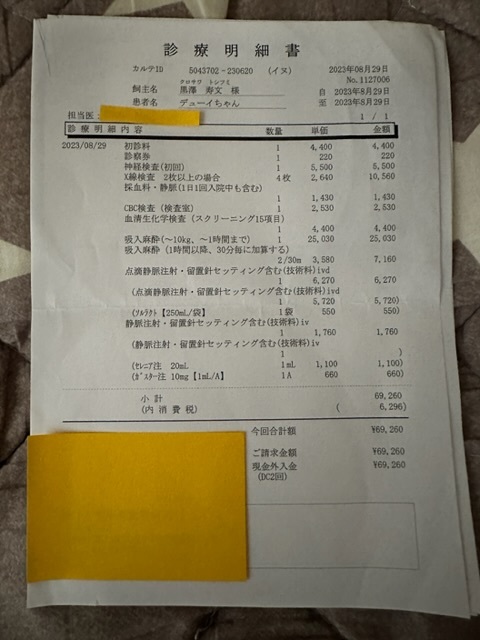

※上記は大学病院で頂いた診断書

※下記は初診かつ、会陰形成術をして頂く動物病院より発行して頂いた診断書、治療計画書

実際にかかった治療費

大学病院での検査

大学病院での手術、入院費